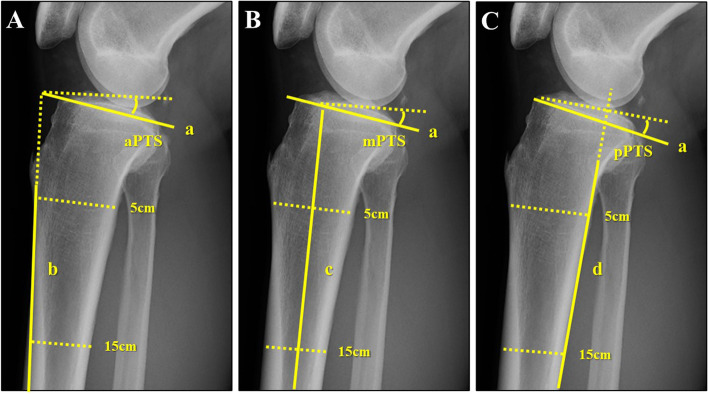

This study only used a plain true lateral view of the knee joint to evaluate PTS. To minimize the influence of different measurement methods in PTS evaluation, the following three methods were used [24]: PTS was defined as the angle between the tangent line to the medial tibial plateau and a line perpendicular to the three anatomic reference axes (the anterior cortical axis [ACA], proximal anatomic axis [PAA], and posterior cortical axis [PCA]). It was denoted as anterior PTS, middle PTS, and posterior PTS (aPTS, mPTS, pPTS, respectively) (Fig. 2). ACA was defined as a line connecting two points, 5 cm and 15 cm distal to the knee joint, on the anterior cortical line of the proximal tibia; PAA was defined as a line connecting the midpoint of the anteroposterior cortical diameter, which was 5 cm and 15 cm distal to the knee joint. PCA was defined as a line connecting two points, 5 cm and 15 cm distal to the knee joint, on the posterior cortical line of the tibia. Measurements were performed by a single orthopedic surgeon (KT) who was blinded to patient characteristics (right or left difference, leg dominance, with or without ACL injury, etc.). The left–right differences in PTS were compared between the control and ACL injury groups. Similar comparisons were made between the injured and non-injured leg and the dominant and nondominant leg in the ACL injury group. As there are numerous studies showing a difference of 2–3 degrees in PTS with and without ACL injury [21, 22, 27], patients with a difference in PTS of ≥ 3° were considered to have a meaningful PTS laterality. These patients were classified into subgroups with or without laterality. The proportion of large left–right PTS difference was compared between the control and ACL-injured groups, as well as between the injured and non-injured side and dominant and nondominant leg in the ACL injury group.

Fig. 2.

The three methods used for the measurement of PTS as the cosine angle formed by the tangent to the medial tibial plateau (Line a) and perpendicular to each reference axis. A aPTS: the angle between lines a and b. B mPTS: the angle between line a and c. C pPTS: the angle between line a and d. a = tangent line to the medial tibial plateau, b = line connecting two points 5 cm and 15 cm distal to the knee joint on the anterior cortical line of the proximal tibia, c = line connecting two points 5 cm and 15 cm distal to the knee joint on the midpoint of the anterior/posterior cortical surface of the proximal tibia, d = line connecting two points 5 cm and 15 cm distal to the knee joint on the posterior cortical line of the proximal tibia. PTS = posterior tibial slope, aPTS = anterior PTS, mPTS = middle PTS, pPTS = posterior PTS